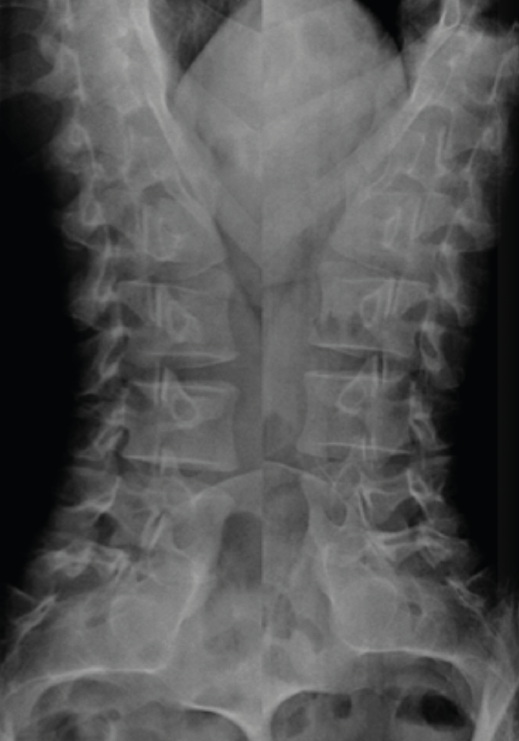

La TAC visualiza con bastante precisión el tejido óseo, siendo claramente superior a la RM para ello. También permite visualizar los tejidos blandos intra- y paraespinales, aunque la RM es muy superior en la evaluación de estos tejidos, por lo que está siendo desplazada por esta para el estudio de los problemas discales, degenerativos y radiculomedulares (Figura 11).

Entre las principales indicaciones de la TAC, se incluirían la sospecha clínica de hernia discal (Figura 12)(26), la estenosis del canal vertebral lumbar, la fractura vertebral lumbar, los tumores vertebrales, la valoración posquirúrgica tras una cirugía de artrodesis vertebral lumbar y la sospecha de una sacroileitis en el contexto clínico de una posible espondiloartropatía inflamatoria. También es muy útil como herramienta auxiliar en determinados procesos diagnósticos, como por ejemplo en la biopsia de una zona sospechosa y en el diagnóstico postoperatorio de la correcta colocación de implantes en la columna vertebral.

Al igual que en la radiología simple, muchos pacientes asintomáticos presentan imágenes anormales en la TAC. En el estudio de Wiesel et al.(25), más del 35% de las TAC de columna lumbar en personas asintomáticas eran patológicas. Por ello, los expertos advierten de la necesidad de correlacionar adecuadamente los hallazgos de la TAC con la sintomatología referida por el paciente.

La sobrevaloración de las imágenes sin una correcta valoración clínica puede conducir a errores diagnósticos y terapéuticos de importancia, oscilando desde restricciones severas de la actividad física y laboral, indicaciones terapéuticas o rehabilitadoras inadecuadas, y hasta intervenciones quirúrgicas no indicadas.